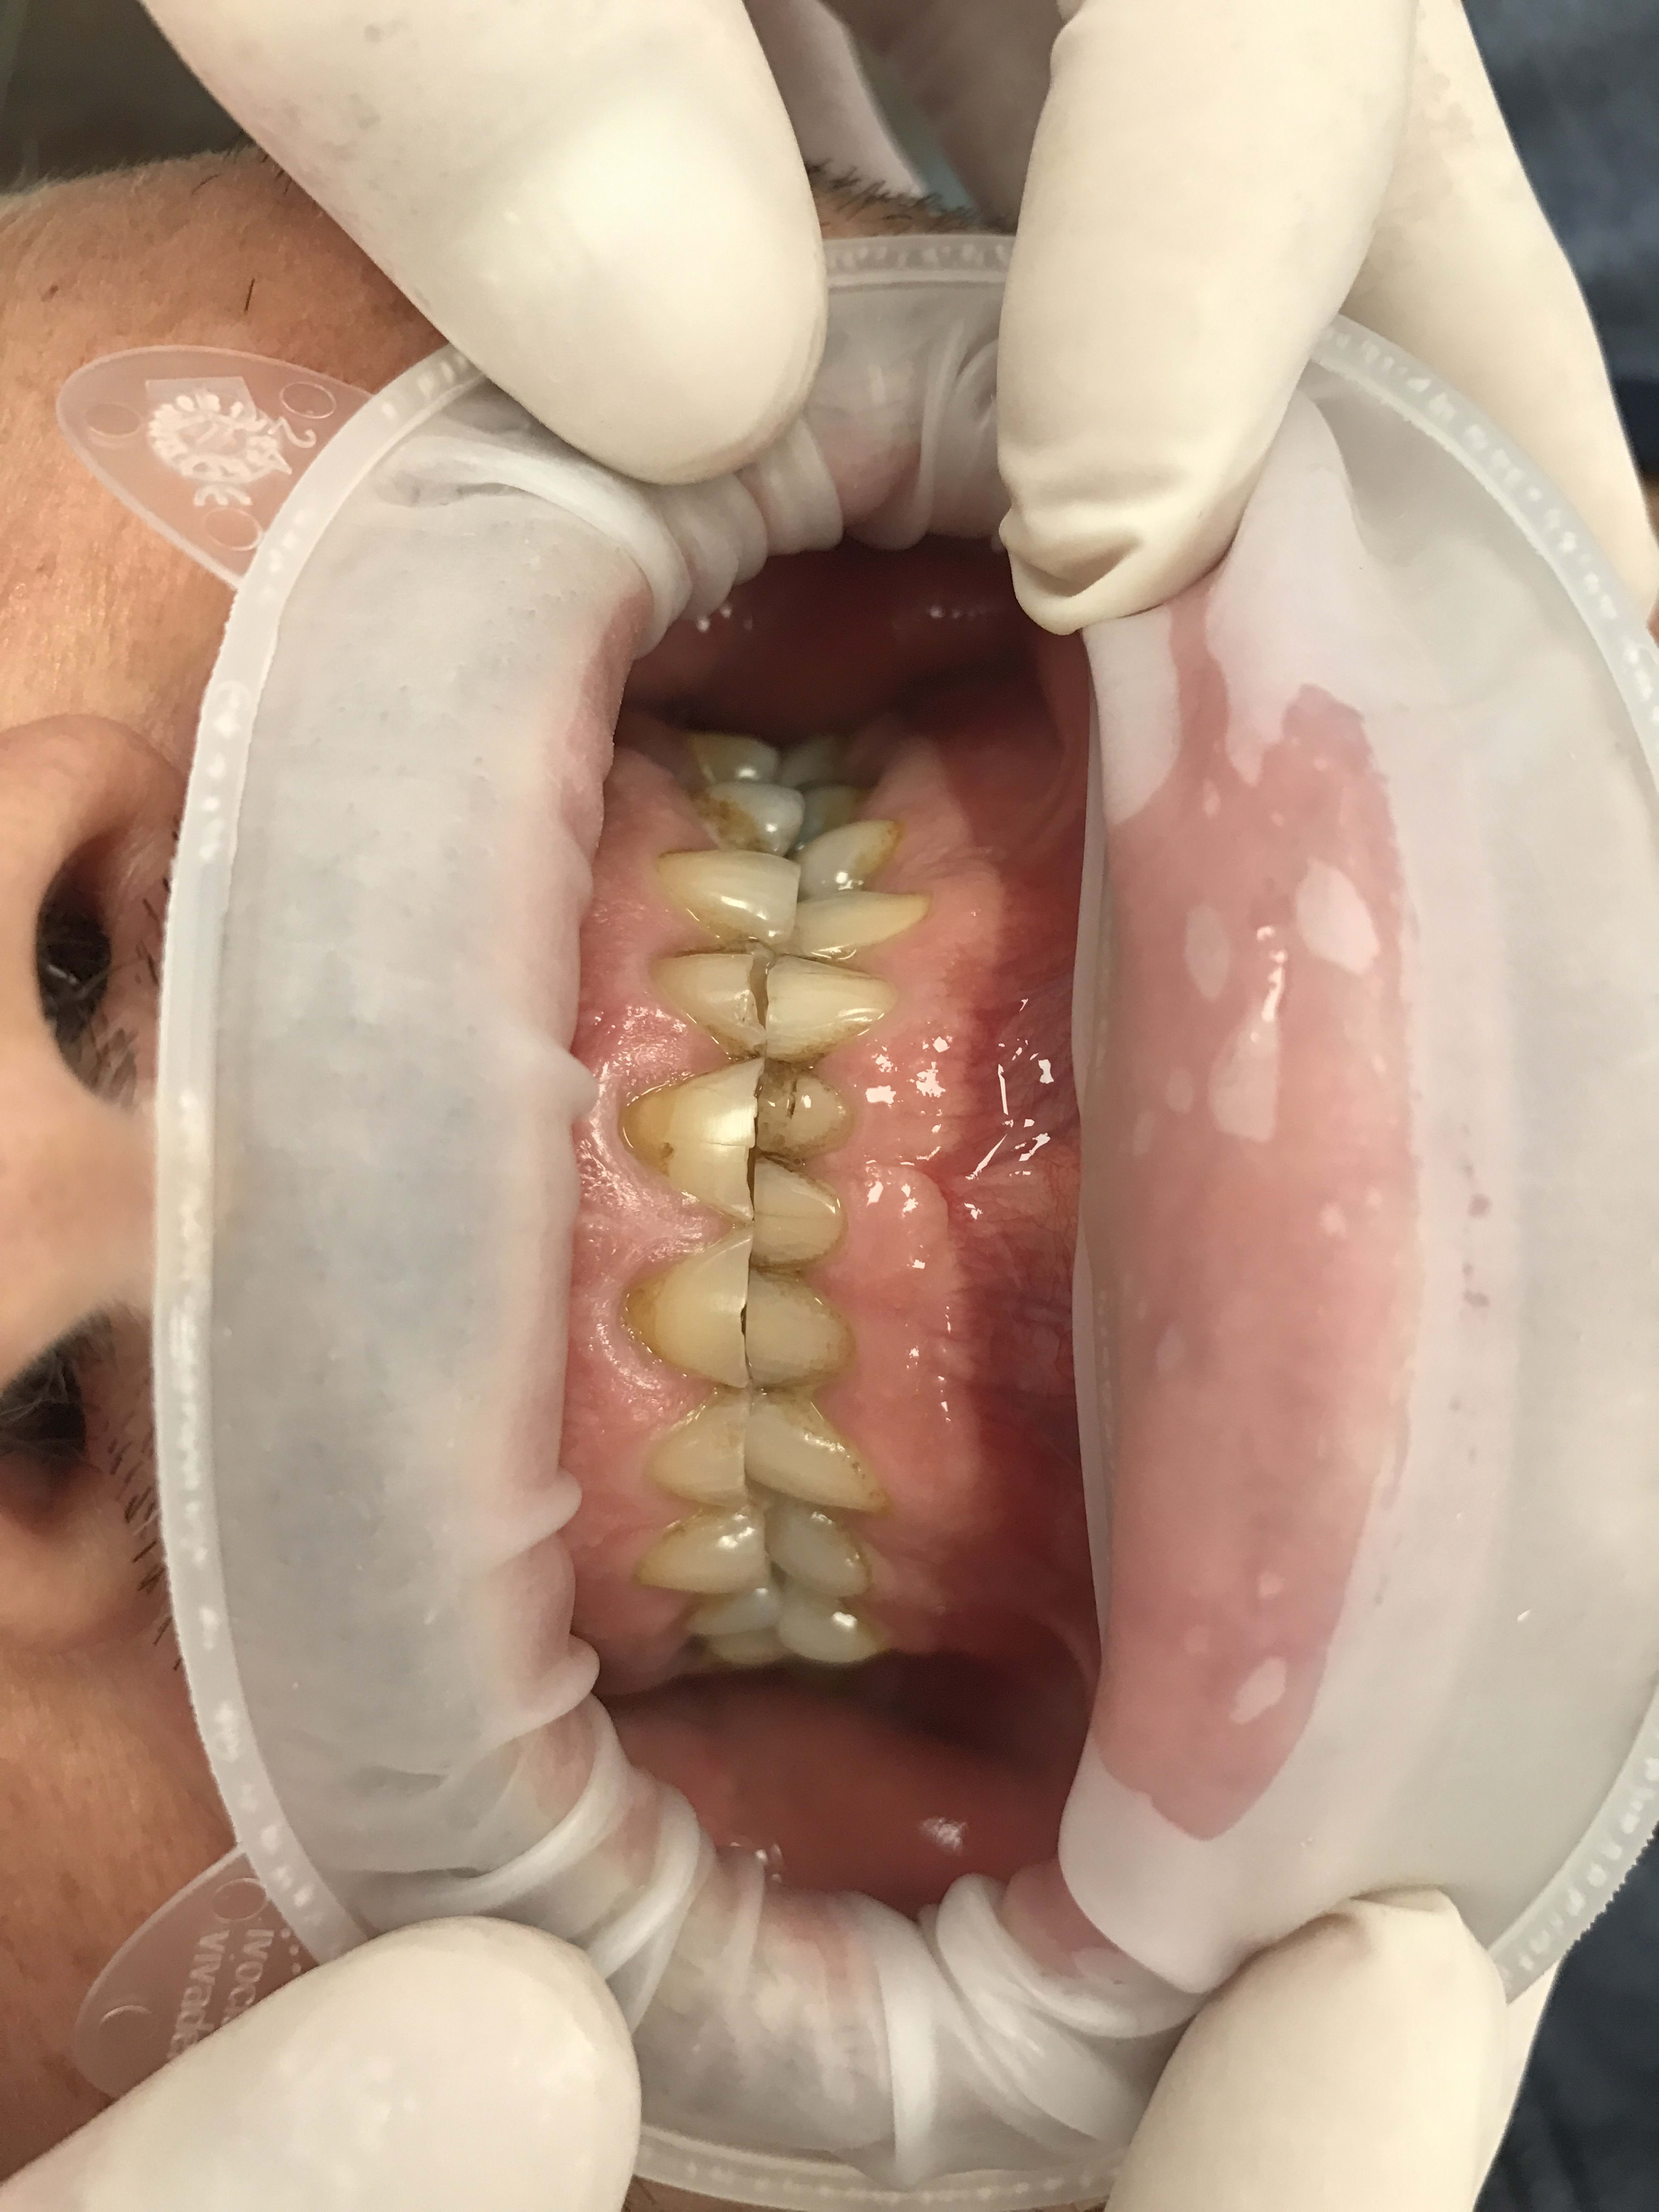

Restauration globale sur un patient qui bruxe?

Cela fait bien longtemps qu'il bruxe et a usé toutes ses dents, n'a plus de calage.

Je pensais faire suite au rte et à la pose des implants un wax up mock up avec facettes en antérieure et table top/couronnes en postérieur, et augmentation de la dvo de plusieurs mm.

Ensuite quels matériaux utuliser pour les restauration connaissant le passé bruxo du patient?